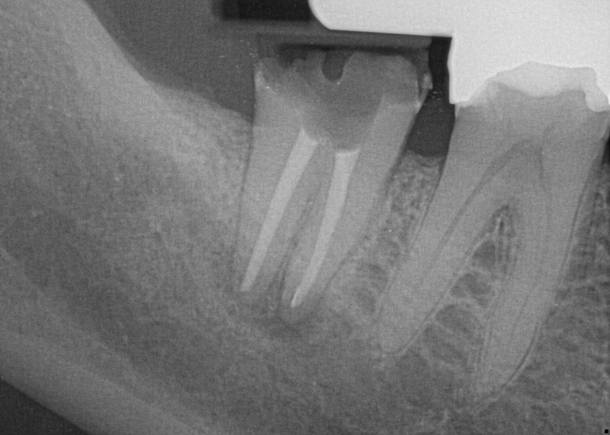

Fig 7. Primary endodontic and secondary periodontal lesion, mandibular second molar.

Figure 7

Treatment of combined endodontic and periodontal lesions does not differ from the treatment of either an endodontic lesion or a periodontal lesion. The part of the lesion sustained by the root-canal infection can usually be expected to resolve after proper endodontic treatment. Timing of the completion of the root-canal therapy, medicaments used, and assessment of restorability are considerations for the long-term success and survival of the tooth.7 Figures 7, 8, and 9 represent the timing of completion and restorative decision-making to complete all therapies.

In Figure 7, the periapical radiograph identifies the presence of the combined endodontic-periodontal lesion developing due to a carious lesion beneath an existing vintage gold crown with ill-fitting margins. Intraoral examination revealed a fistula developing and moderate pain on percussion and mastication. After occlusal access and clear visualization of the canals, the canals were shaped using the rotary files, with precautions taken not to perforate or enlarge the apical foramen. Maintaining the endodontic therapy within the canals prevents the infection from being introduced into the surrounding periodontium. In this case, calcium hydroxide medicament was placed into the canals and evaluated 30 days postoperatively.8